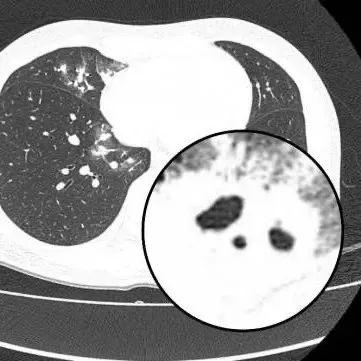

胸部CT顯示其雙肺多發感染

伴多發空洞形成

醫生查房時,捕捉到CT上形似“鬼臉”的特殊影像(即“鬼臉徵”),並伴有“暈倫徵”,高度懷疑隱球菌肺炎。醫生追問夏女士近期是否曾接觸鳥類、禽類及飼養寵物,夏女士否認。

在免疫功能正常的患者中,肺部常見的表現爲單發或多發的結節,有時伴有暈徵(指結節周圍的低密度環),結節內可能見到空洞,胸膜下多見。在免疫功能缺陷(如惡性腫瘤、白血病等)的患者中,可能表現爲瀰漫的、大片的肺炎樣改變。